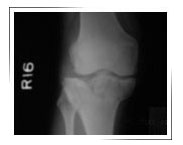

Fracture lateral condyle with depression :

Before surgery X-ray